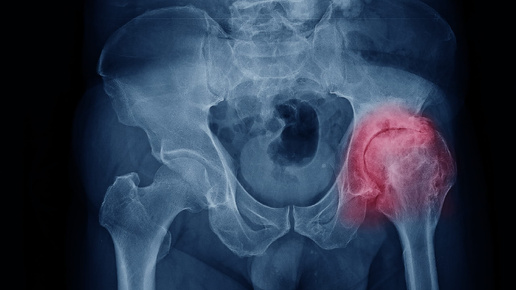

Когда впервые появляется ноющая боль в бедре, особенно после долгой прогулки или подъёма по лестнице, многие списывают это на усталость или «возраст». Но если дискомфорт не проходит, а со временем усиливается, становится трудно надевать обувь, сидеть за рулем или просто подниматься с дивана — пора задуматься: а не коксартроз ли это? Это слово звучит пугающе. Оно ассоциируется с хрустом, хромотой, операциями, потерей подвижности. Многие считают, что коксартроз — это приговор: раз начался, значит, неизбежно приведёт к инвалидности...

Люди старше 40 лет в той или иной степени испытывают боли в тазобедренном суставе. Зачастую причиной этому служит коксартроз(артроз тазобедренного сустава). Коксартроз обычно затрагивает людей с избыточной массой тела, ведущих малоподвижный образ жизни, и конечно людей, которые могут собрать эти причины воедино, это - люди преклонного возраста. Пациентов, которые страдают коксартрозом обычно беспокоят боли при движение в тазобедренном суставе, дискомфорт, ноющи боли по ночам, чувство что с утра нужно разработать сустав, "расходится"...